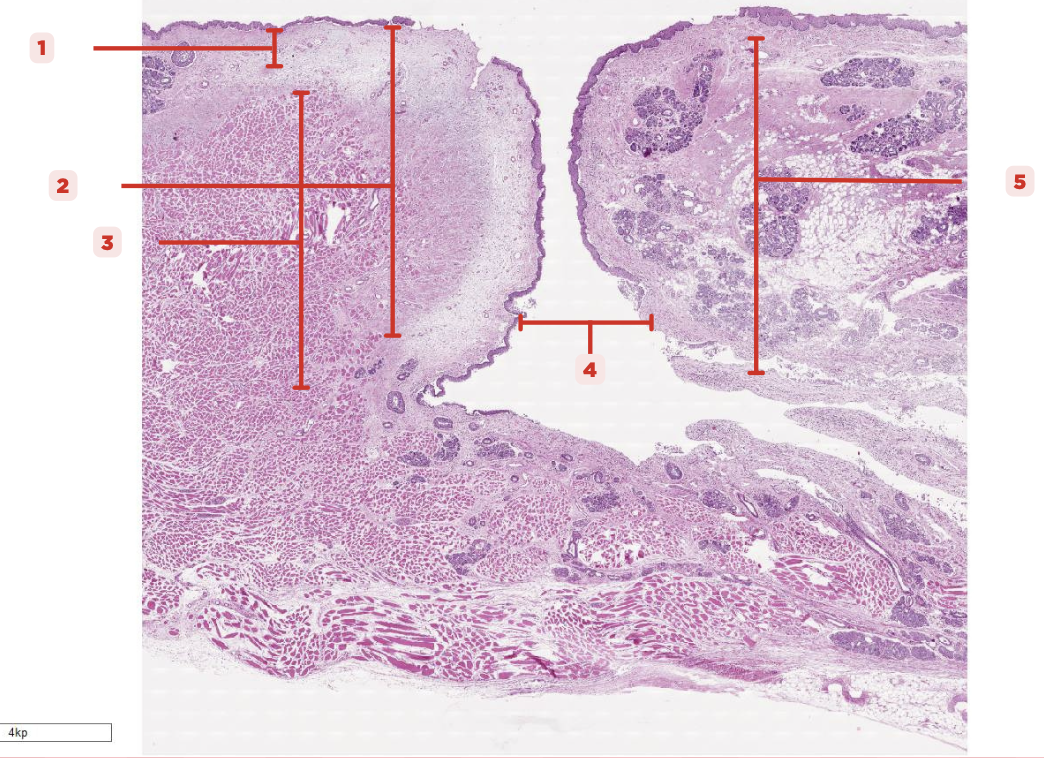

Identify the structure labeled as 1.

Laryngeal Ventricle

Space that separates the true and false vocal cords (#4)

True Vocal Cord

The #2 consists of a lamina propria that includes the vocalis ligament and a group of skeletal muscles known as the vocalis muscle.

Vocalis Ligament

Identify the structure labeled as 1.

True Vocal Cord

Identify the structure labeled as 2.

Vocalis Muscle

Identify the structure labeled as 3.

Laryngeal Ventricle

Identify the structure labeled as 4.

False Vocal Cord

Identify the structure labeled as 5.